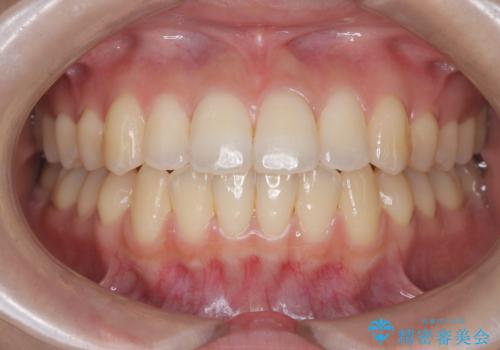

前歯の突出を防ぎながらガタつきを解消。上下左右4番抜歯による審美ワイヤー矯正